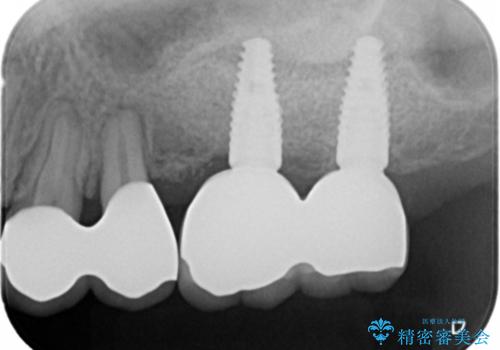

- 110万円(インプラント×2・チタンカスタムアバットメント×2・ジルコニアクラウン×2・仮歯×2・ 骨造成・サイナスリフト)費用は治療当時の料金となります

インプラントの仕上がりを見越して、ただ埋入するだけではなく長期的な予後を見込むには清掃のしやすい環境を整備することが大切です。

今回は大きく吸収してしまった歯槽骨をしっかりと造成することで、歯間ブラシを行いやすいインプラント周囲環境を整備することができました。